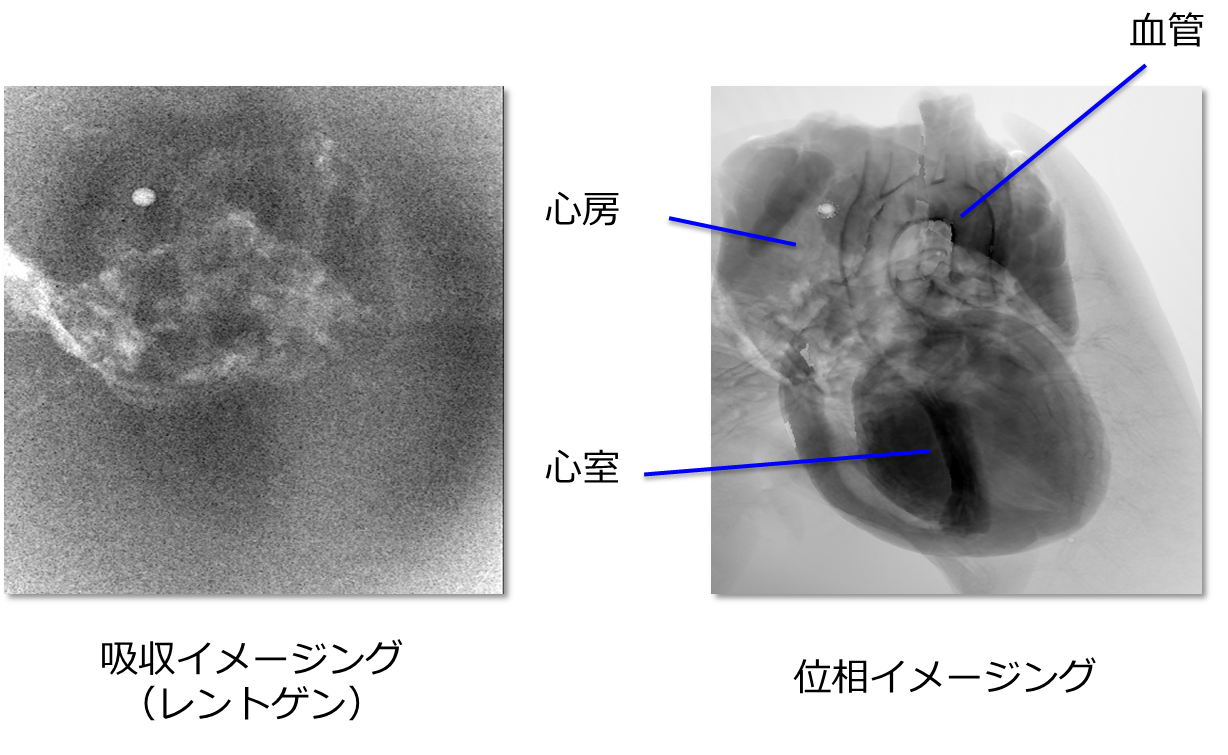

図2は同じX線の照射線量で取得したラット心臓の2次元像です。吸収コントラスト像では太い血管が僅かに見えている程度ですが、位相コントラスト像では、血管に加えて、心房や心室が非常に鮮明に可視化できていることがわかります。このように、位相イメージングは従来のレントゲンの限界を打破する非常に大きな可能性を秘めているイメージング法です。

図2 ラット心臓の撮像例。吸収コントラスト像(左)と位相コントラスト像(右)